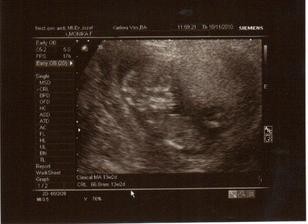

krasne 3D sono 🙂